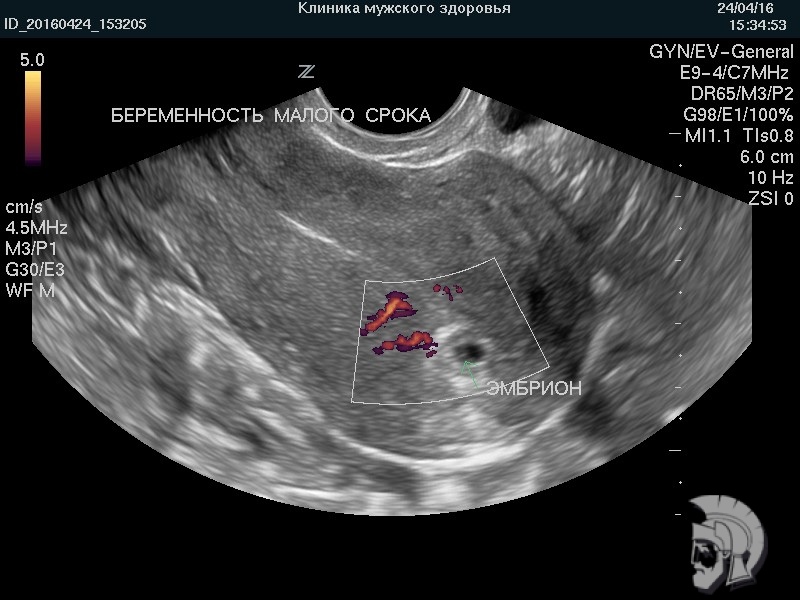

| Фото беременности малого срока. Эмбрион в виде пшеничного зерна указан стрелкой. При исследовании в режиме ДОППЛЕРа определяется маточный кровоток |

Ответ: УЗИ беременности на ранних сроках позволяет определить форму плодного яйца и строение эмбриона, сердцебиение и особенности кровоснабжения эмбриона и плодного яйца, состояние шейки матки и тонус матки. На основании анализа вышеупомянутых данных врач УЗИ делает вывод о правильности развития эмбриона и течения беременности на ранних сроках.